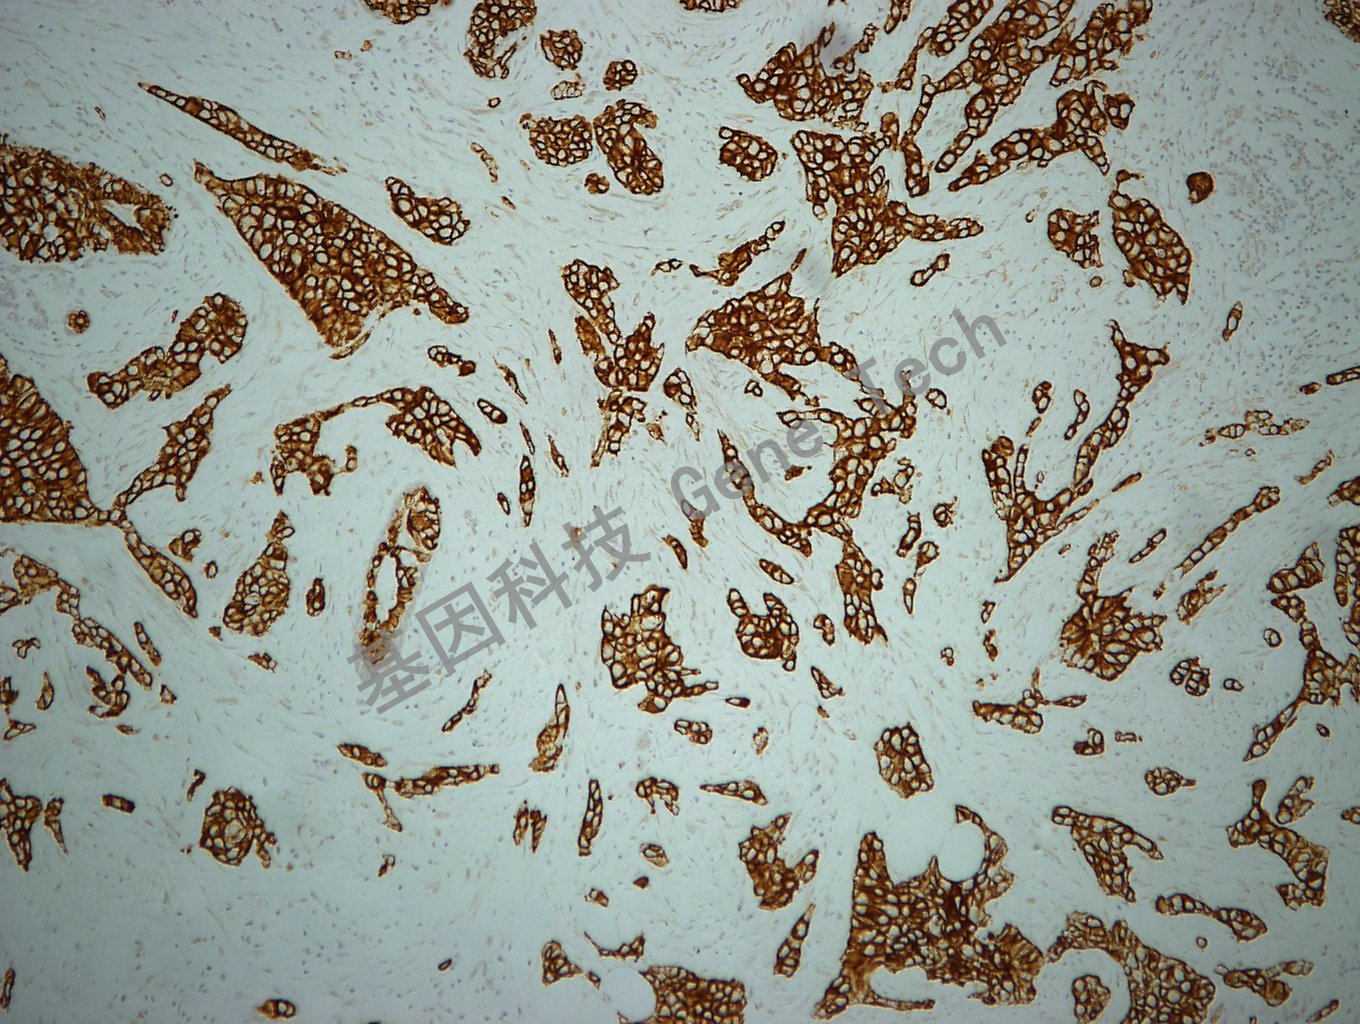

阑尾石蜡切片,用 CK19(GM0888)染色,细胞浆阳性,DAB 显色。(10×)

乳腺癌石蜡切片,用 CK19(GM0888)染色,细胞浆阳性,DAB 显色。(10×)